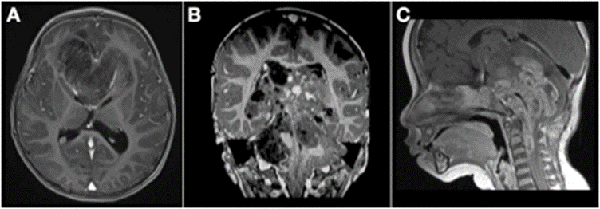

Analizando por separado los resultados de anatomías patológicas vemos que los ATRT, meduloblastomas y ependimomas tuvieron una supervivencia del 32% a los 5 años (Figuras 3 y 4) y los pacientes con tumores embrionarios, PNET, carcinomas y papilomas atípicos de plexos coroideos y pineoblastomas presentaron una mortalidad del 100% a los 5 años (Figuras 5 y 6). Por otro lado, los papilomas de plexos coroideos, lesiones más frecuentes en el grupo 1, tuvieron un 100% de supervivencia a los 10 años, al igual que los astrocitomas y gliomas de bajo grado (Figuras 7 y 8).

Figura 3: A) Paciente de 11 meses de vida, sexo masculino, que presentó macrocefalia, irritabilidad y vómitos, IRM de cerebro que mostró extensa lesión cerebelosa de aspecto nodular con intenso realce con el contraste endovenoso. B) IRM corte sagital de dicha lesión. C) IRM de cerebro postquirúrgica luego de dos cirugías de exploración y exéresis, diagnóstico de meduloblastoma desmoplásico nodular. Realizó quimioterapia y actualmente presenta un leve retraso neuromadurativo.

Figura 4: A) Paciente de 21 meses de vida, sexo masculino, que consultó por SHE y deterioro del sensorio. IRM de cerebro corte axial que evidenció lesión heterogénea en IV ventrículo y vermis con compromiso de tronco del encéfalo. B) IRM de cerebro corte sagital: ocupación de la totalidad del IV ventrículo. C) IRM de cerebro post quirúrgica, se evidenció exéresis tumoral completa, diagnóstico de ATRT de fosa posterior. Paciente falleció por progresion de enfermedad a los 6 meses.